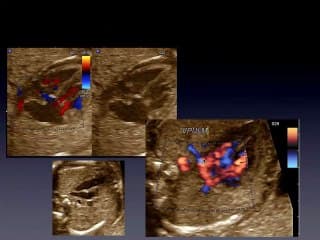

Bernard BENOIT nous éblouit comme d'habitude avec des images "trop proches du réél, ce qui peut s'avérer parfois troublant pour les patientes... Il nous montre les possibilités nouvelles en 3D et 4D pour approcher les diagnostics de dysmorphies. Il nous montre des exemples de T21 qui sont très explicites avec une grande variabilité de visages. L'échographie 3D est plus un outil de diagnostic que de dépistage. Les limites sont les mêmes qu'en 2D...

L’utilisation de sondes à haute fréquence longue focale devient un complément d’investigation très intéressant pour préciser une image inhabituelle ou anormale. Les structures de la face de prêtent bien à ce mode d’imagerie dès 18 SA pour les patientes présentant un risque de récurrence d’une affection malformative touchant la lèvre supérieure, le palais, la mandibule, les globes oculaires et les oreilles.